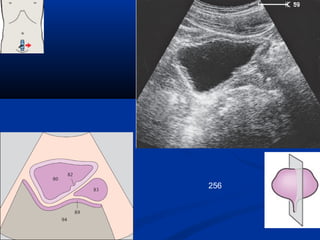

256